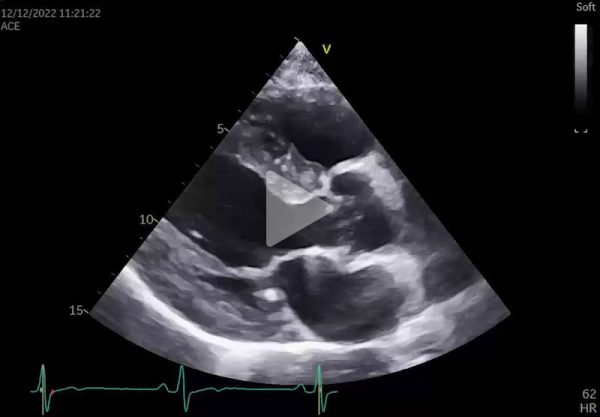

Une échographie cardiaque est demandée dans le bilan étiologique et devant l’aspect ECG (Vidéos 1 et 2, et Figure 2):

Vidéo 2 - Coupes 4 cavités (ETT)

L’échographie cardiaque montre:

- Hypertrophie circonférentielle de 17 mm (Figure 6)

- Diminution du strain de la paroi postéro-latérale évocatrice d’une maladie de Fabry sans élément pour une amylose (notamment pas de gradient base-apex) (Figure 2)

- Dilatation à 44 mm du sinus de Valsalva

- Remodelage VG concentrique ou HVG sans obstruction intra-VG à l’état de base

- Hypo- voire akinésie de la paroi inféro-latérale du VG (en rapport avec la fibrose) et altération du strain, particulièrement au niveau du segment inféro-latéral

- Aspect épaissi, infiltré des valves mitrale et aortique, avec régurgitation légère à modérée

- Hypertrophie du VD et des muscles papillaires

- Dilatation légère à modérée du sinus de Valsalva et de l’aorte ascendante dans les formes avancées de la maladie.